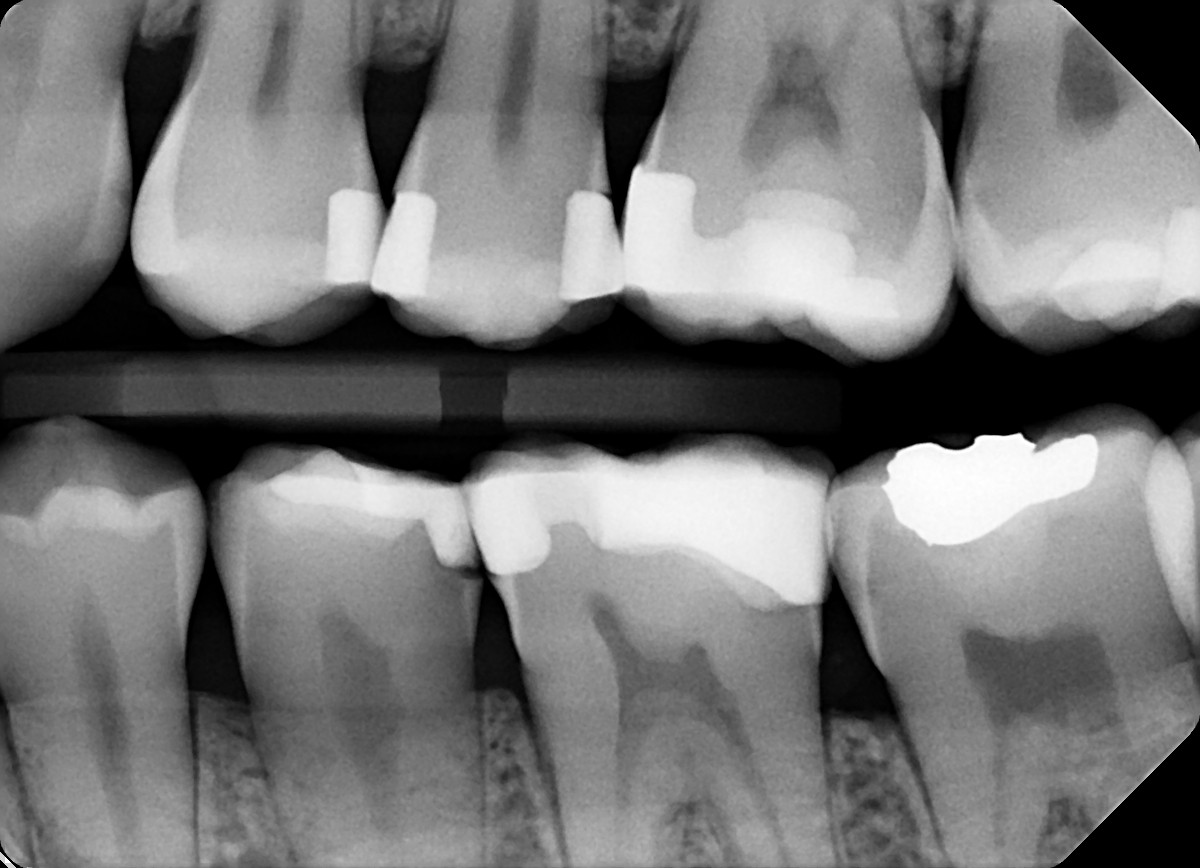

2. In the X ray bellow for which jaw periodontal bone loss is evident?